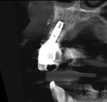

In this case, a dental implant that had been placed 10 years prior was functional, stable, and esthetically acceptable to the patient. However, a significant fistula was present on the facial-apical aspect of the ridge in the maxillary lateral incisor area. This area was painfully sensitive to touch and demonstrated purulence when squeezed. To evaluate the lesion, first, a conventional digital radiograph was acquired, which revealed an apical radiolucency at the apex of the implant (Figure 1). Further analysis using cone-beam computed tomography (CBCT) demonstrated a fistula from that site to the oral environment (Figure 2). Treatment options were discussed, including removal of the implant, followed by grafting, a healing period, and replacement of the implant and implant-retained crown. If this option was selected, a transitional appliance would need to be created. Another option was to attempt to salvage the implant and implant crown by treating the infection and grafting the site to create a new boney wall and eliminate the fistula. Ultimately, the patient accepted this option to attempt to salvage the fixture and crown.

(2.) Preoperative CBCT analysis demonstrating a fistula from the site of the radiolucency to the oral environment.

Figure 2

(14.) Follow-up 8-week postoperative CBCT analysis of the area demonstrating closure of the diseased site, absence of the radiopaque lesion, and new facial wall formation.

Figure 14